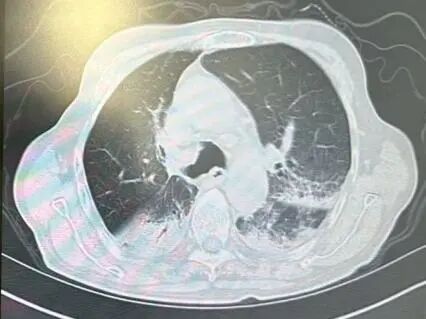

内容提要 近日,市第二人民医院呼吸与危重症医学科宋刚主任团队,成功救治一名98岁高龄、患有罕见隐源性机化性肺炎(COP)的患者。面对高龄、病情复杂、诊治风险高等重重困难,团队凭借精湛医术与丰富经验,帮助老人转危为安,再次彰显了科室在危重症救治领域的强大实力。 挑战一:高龄禁区,敢为人先 患者因发热、咳嗽,伴乏力、气短、喘息等症状来院,此前在当地诊所使用多种抗生素均无效,病因成谜。要明确诊断,支气管镜检查是关键一步,但对近百岁老人而言,此项操作犹如踏入“生命禁区”,风险极高。宋刚主任团队没有退缩,在全面评估、周密预案、充分沟通的基础上,凭借丰富经验成功实施检查,为后续治疗打开了至关重要的突破口。 治疗前患者肺部CT影像 挑战二:罕见病症,迷雾重重 检查结果指向一种罕见疾病——隐源性机化性肺炎(COP)。此病本就少见,好发于50~60岁人群,在近百岁老人中发生更是极为罕见。更为棘手的是,患者还伴有胸腔积液。COP通常表现为发热和肺部影像上的“游走性”阴影,很少合并胸腔积液,这使得诊断工作如雾里看花,难度倍增。 挑战三:病菌分辨,生死抉择 诊断刚明,新的考验接踵而至:患者标本中检出了根毛霉菌。COP的核心治疗是糖皮质激素,若根毛霉菌是致病菌,激素可能引发真菌扩散,用药无疑将导致致命风险。因此,辨别其是“定植菌”还是“致病菌”,成为治疗成败的关键。 宋刚主任团队凭借丰富的临床经验和严谨的诊疗思维,结合患者肺部影像特征、症状及化验结果,综合判断认为该霉菌属于定植菌,从而排除了治疗障碍,确保了后续用药安全。 精心施治,百岁老人转危为安 在后续治疗中,团队如履薄冰,精细平衡抗凝与激素治疗带来的出血、感染等风险,制定个体化方案。经过精心治疗与护理,老人肺部病灶显著吸收,各项指标恢复正常,最终康复出院。 治疗前后肺部CT影像对比,左侧为治疗后,右侧为治疗前。 此次成功救治,充分体现了市二院呼吸与危重症医学科在复杂疑难呼吸道疾病及危重症领域的综合救治能力。面对高龄高风险患者,团队始终以患者为中心,在风险与疗效间精准把握,用技术与责任守护每一位患者的呼吸健康。 人民医院 人民名医 宋刚 主任医师 ·葫芦岛市第二人民医院呼吸与危重症医学科主任 ·辽宁省生命科学学会东北呼吸与危重症医学(PCCM)分会辽宁省基层委员会副主任委员 ·辽宁省细胞生物学学会放射粒子治疗专业委员会理事 ·辽宁省抗击新冠肺炎疫情先进个人 ·辽宁省预防医学会第一届吸烟相关疾病防治专业委员会委员 ·葫芦岛市劳动鉴定委员会专家库成员 ·葫芦岛市医学会呼吸内科学分会第三届委员会副主任委员 专业特色:擅长呼吸系统疑难及急危重患者的救治,如急慢性支气管炎、支气管哮喘、慢性阻塞性肺疾病、肺炎、肺栓塞、肺癌、间质性肺疾病、睡眠呼吸暂停综合征等,尤其擅长有创无创机械通气、支气管镜下相关检查及治疗(TBNA、气道支架置入术、球囊扩张等)、全肺灌洗术等领先技术,发表国家级期刊多篇。 出诊时间:每周二、周四全天 出诊地点:门诊二楼东侧35诊室